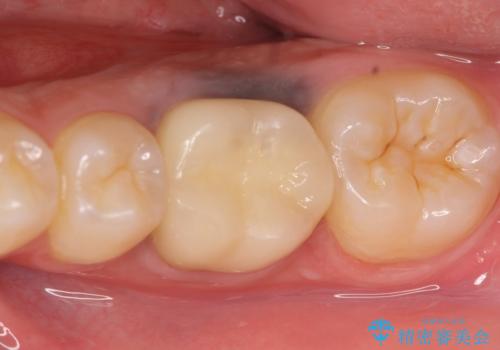

今回用いたオールセラミッククラウンはジルコニアフレームという白い素材の上にセラミックを盛っているため、審美性が非常に高いのが特徴です。

また、ジルコニアは人工ダイヤモンドの材料にも使われているほど高い強度を持っており、そのためオールセラミッククラウンは審美性だけでなく、奥歯やブリッジの補綴も可能とするクラウンです。